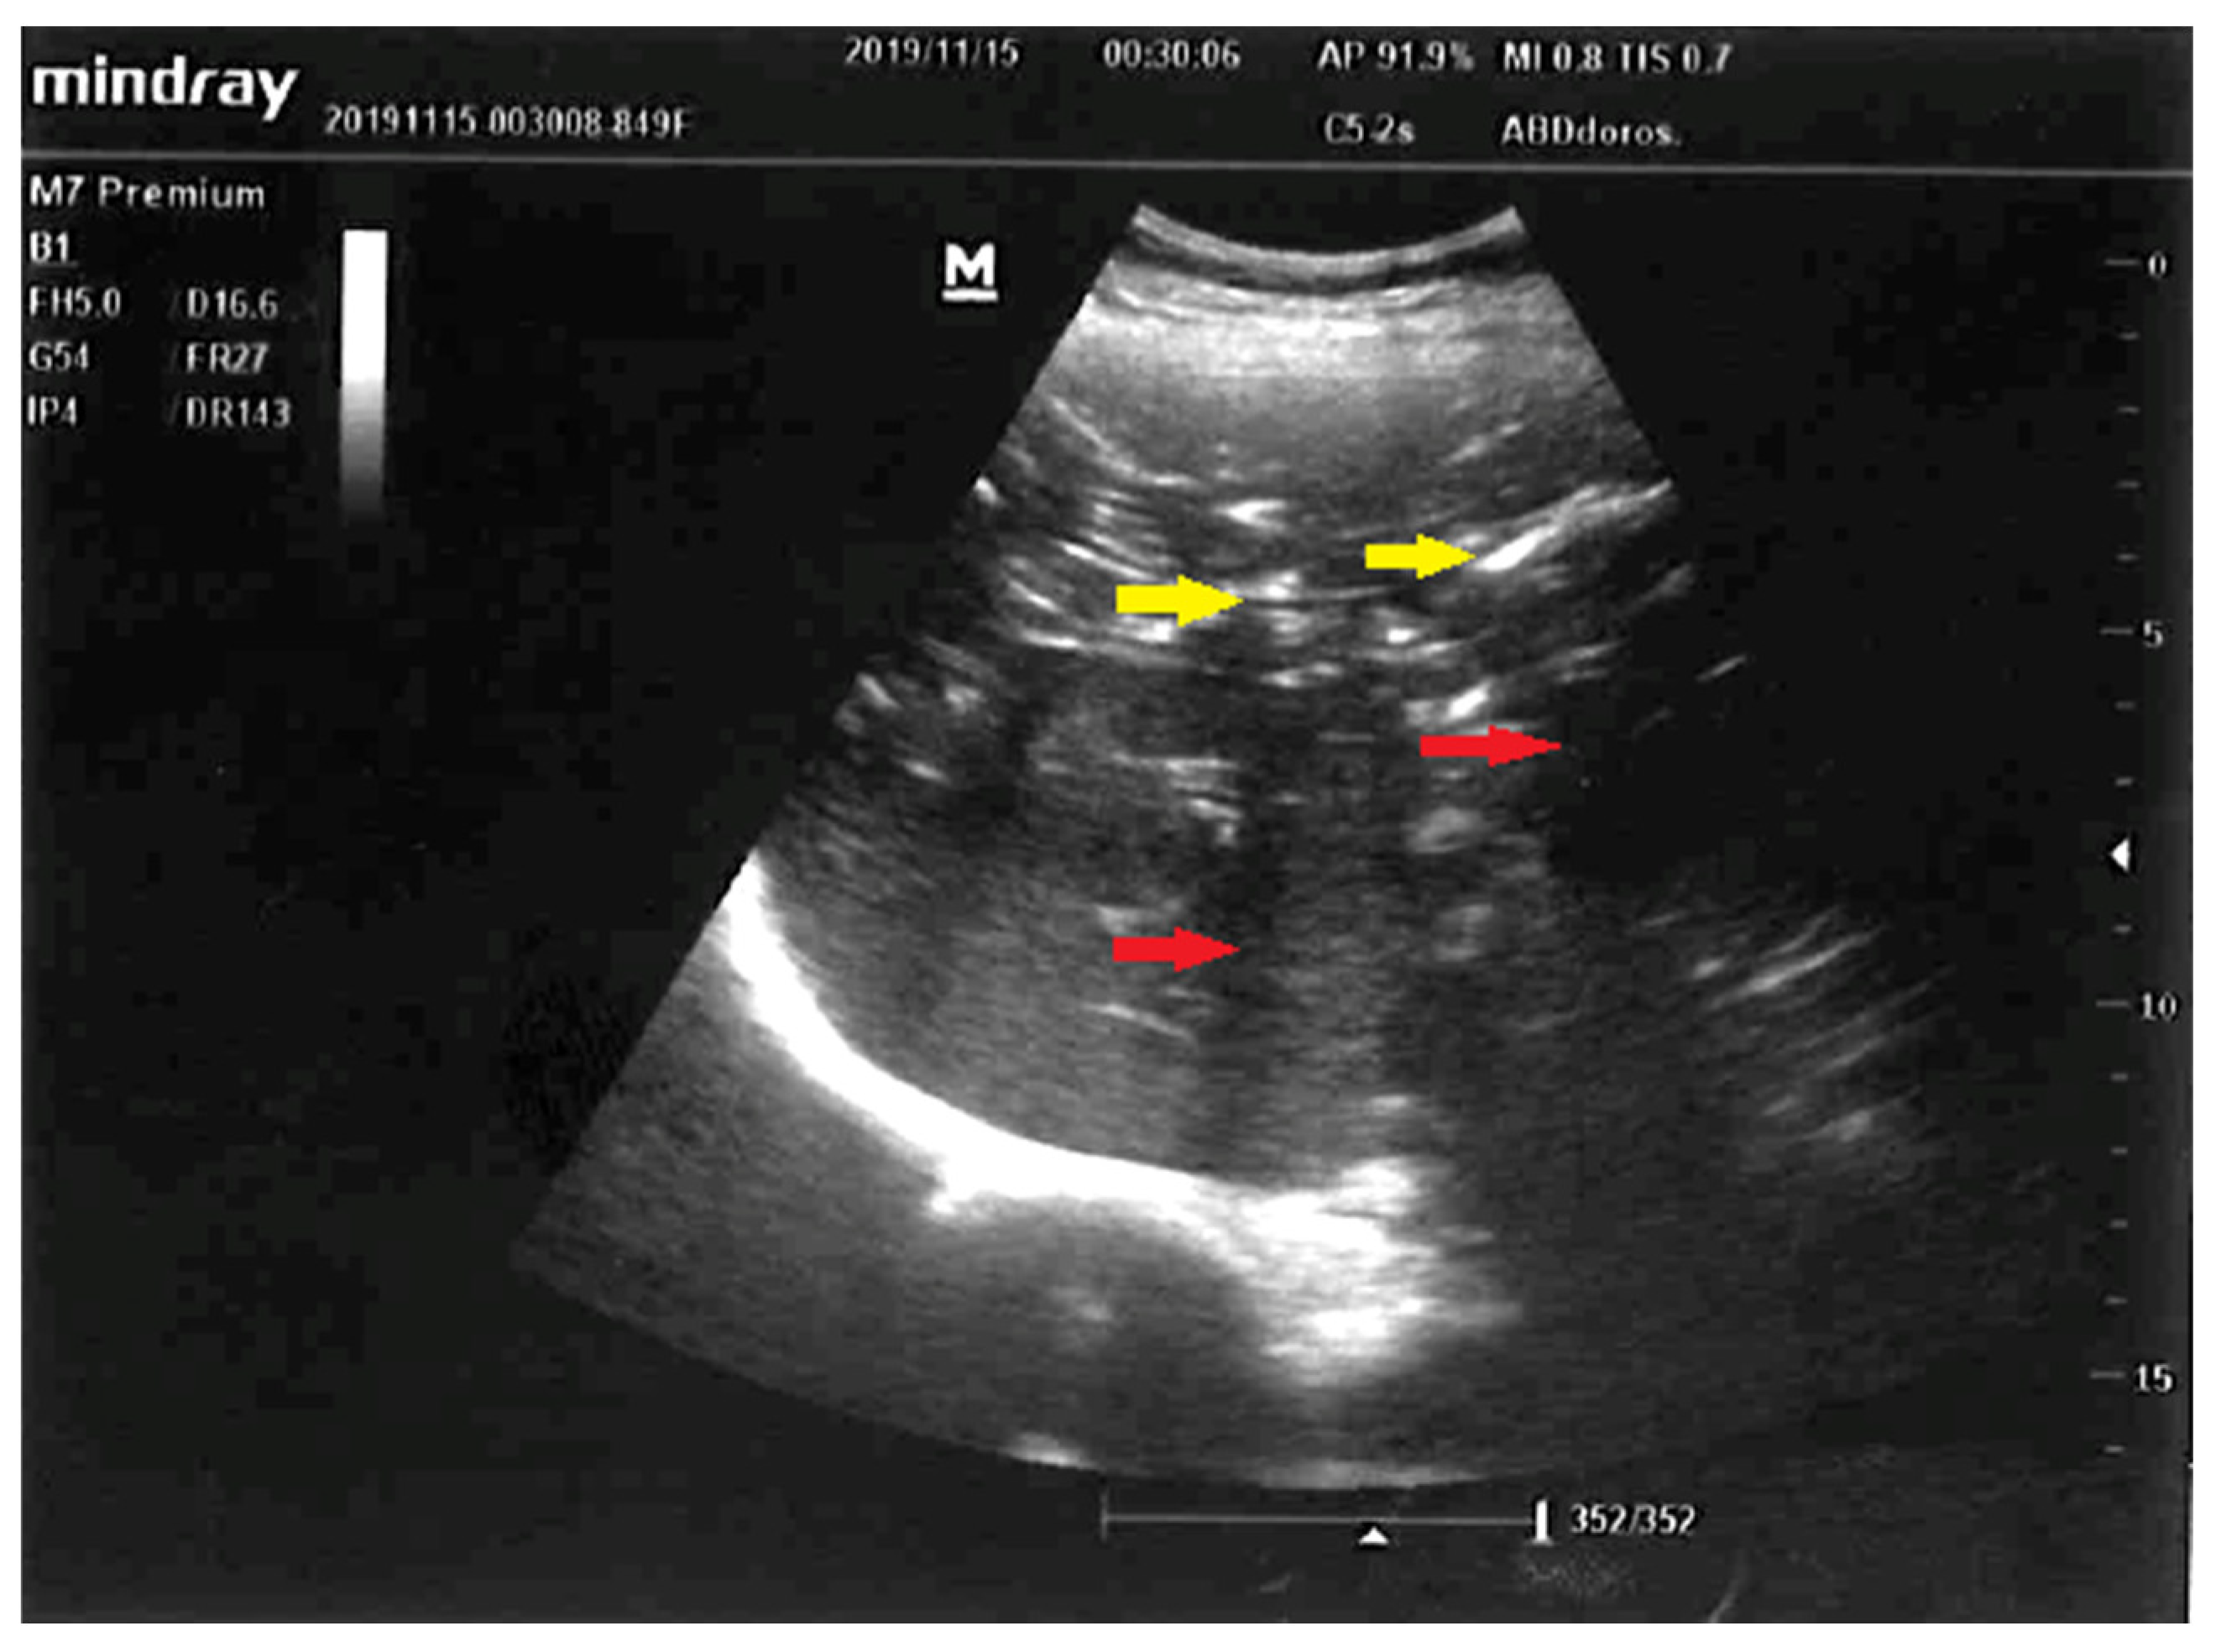

Early liver ultrasound (US) performed to find a source of sepsis in a 52-year-old female suspected to have developed intraabdominal sepsis. Visualized here are: normal-sized liver, punctuated hyperechoic foci with anti-gravitational distribution (yellow arrows) casting acoustic shadows (red arrows). Due to characteristic appearance on liver US, the most likely diagnosis was hepatic portal venous gas (HPVG) [1,2]. Other less likely diagnoses were: pneumobilia due to cholangitis, hepatic micro-abscesses, and punctuate calcifications. Hepatic portal venous gas detected by US following liver transplantation or in suppurative cholangitis were described previously [3,4]. Although presence of mesenteric ischemia and gas in the portal venous circulation was previously revealed with computed tomography [5,6], in our case early abdominal US was performed, what expedited definite diagnosis and targeted treatment: choice of empiric broad-spectrum antibiotics and explorative laparotomy. This is the first time, to the best of our knowledge, that HPVG was visualized with US in the setting of acute mesenteric ischemia.